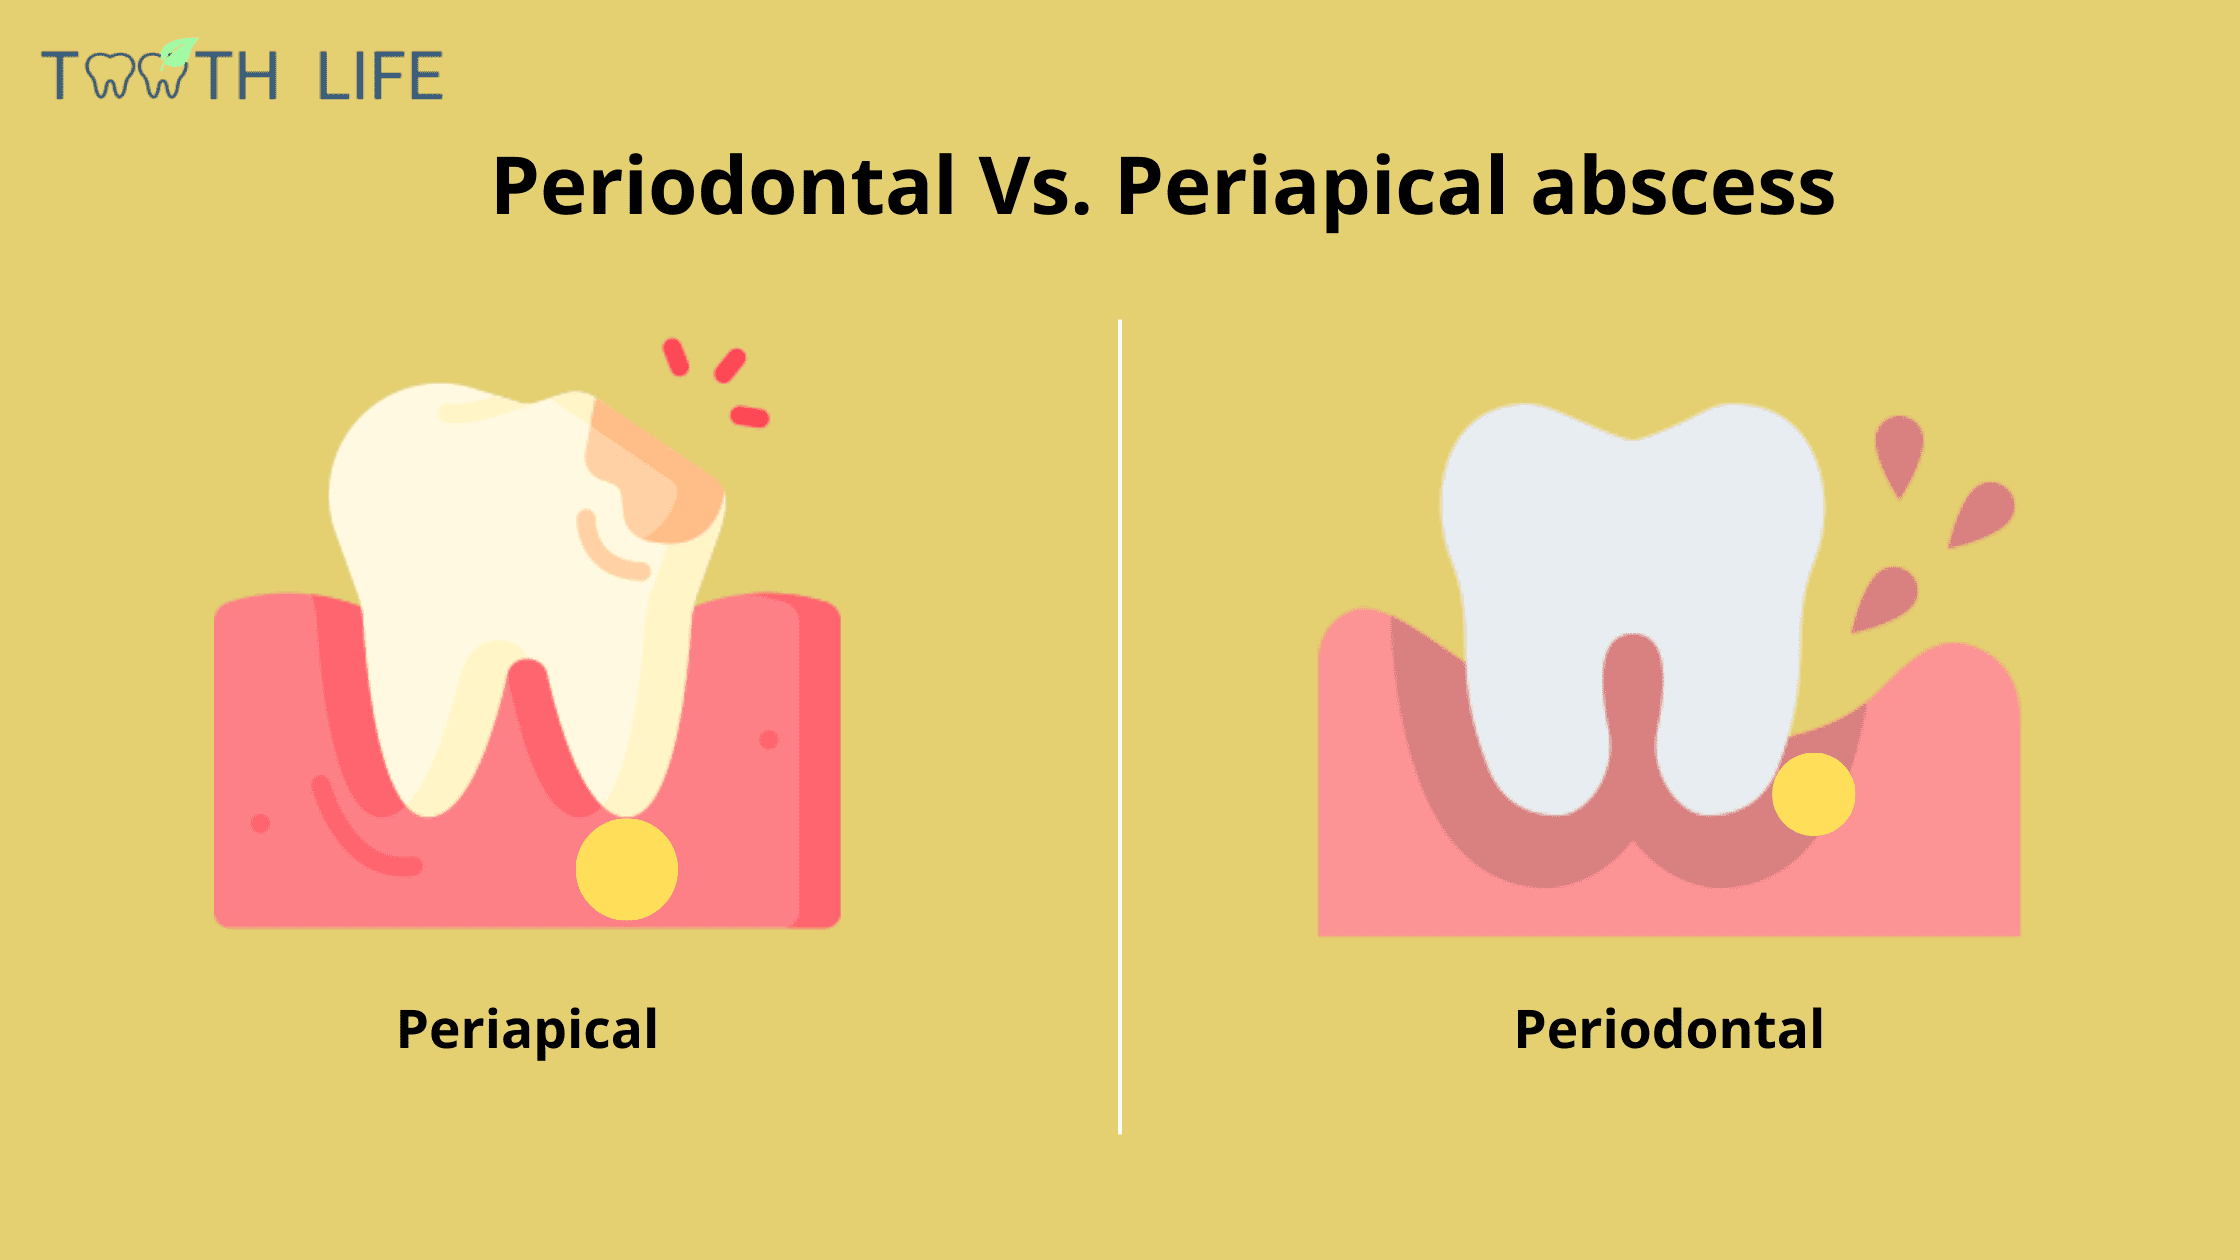

A Gum Abscess With no Pain Can be Worse than you Think. Here’s Why

It’s usually caused by an infection and produces pus Phlegmon is an area of soft tissue or fluid density effacing or displacing usual fat or other connective tissue and shows variable enhancement However, an abscess typically has a. A phlegmon is a localized area of acute inflammation of the soft tissues

A phlegmon results when an acute infection is not confined as in the case of abscess

Instead the infection spreads along tissue planes and between muscle fibers. Phlegmon is a serious skin infection that affects the soft tissues, leading to inflammation and a collection of pus It is often caused by bacteria entering the skin through a. This article explores the causes, symptoms, diagnosis, and treatment of phlegmon, including its classifications based on clinical course, severity, location, cause, pathogenesis,.